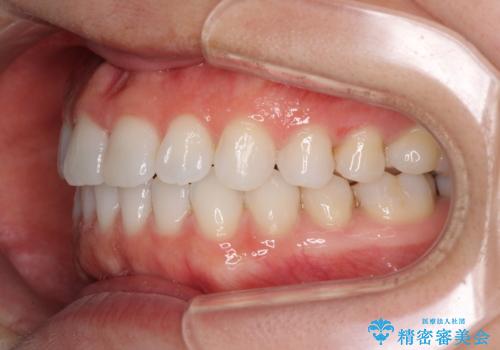

- 上下の前歯の反対咬合を気にして来院された患者様です。

インビザラインを用い、下顎はIPR(歯と歯の間を削る)と歯列全体を後方に移動させ、上顎は前歯を持ち上げることで、反対咬合を改善していくこととしました。

インビザラインによる反対咬合の改善は、上の歯が下の歯を乗り越えていく期間に咬み合わせが非常に不安定となり、治療が長期化することがあります。

こちらの患者様も、一時的に前歯でしか咬めない時期がありましたが、比較的早く咬み合わせが安定し、1年ほどで治療を終えることができました。